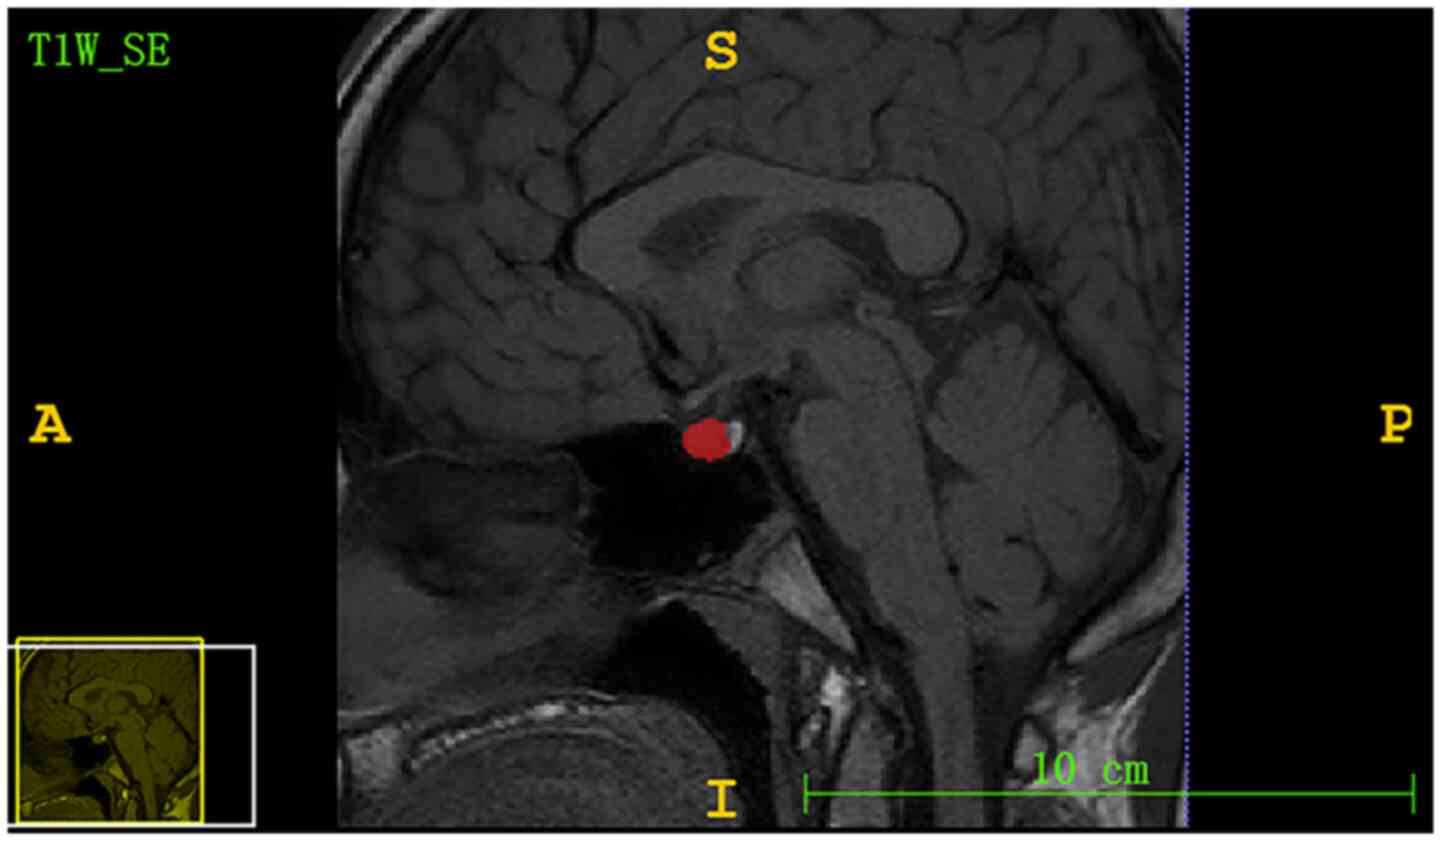

The region of interest (ROI) from the pituitary gland was segmented by a radiologist with 6 years of experience using ITK-SNAP software (version 3.6.0; www.itksnap.org). The ROI included the largest level of the sagittal T1 non-enhanced sequence, which displayed the pituitary stalk, as shown in Fig. 2. A total of 57 MRI textures (12 histogram features, nine form factor features and 36 grey level co-occurrence matrix features) were extracted from the pituitary gland ROI using Matlab R2014a software (MathWorks) and C++ language was used to write features.

Figure 2

Midline sagittal images of the pituitary gland in a child with growth hormone deficiency. The red area represents the region of interest.